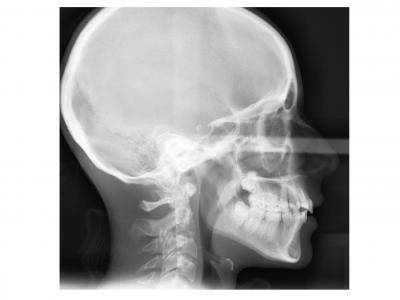

Voici les deux patientes traitées

Ici, dans les deux cas, les deuxièmes prémolaires ont été extraites et les traitements ont duré 18 mois.

Dans le premier cas, la béance s'est fermée spontanément (pas prévu au départ) sans rééducation, sans appareil de contrainte linguale, ni élastique. Il semblerait que le gain de place a permis aux incisives de se redresser spontanément et donc de fermer la béance. La fermeture de la béance, la normalisation de l'environnement anatomique a permis à la langue de se mettre à travailler correctement. Pour le sens transversal, la correction a été aussi spontanée. Juste une minivis dans le secteur 1 a été placée pour recentrer mon milieu (ancrage maximal recherché au départ). Les finitions auraient pu être meilleures. Elle finit avec une légère classe II (on va dire qu’elle est surcorrigée :)). Le traitement a terminé plus tôt que prévu (24 mois annoncé), car problèmes de santé.